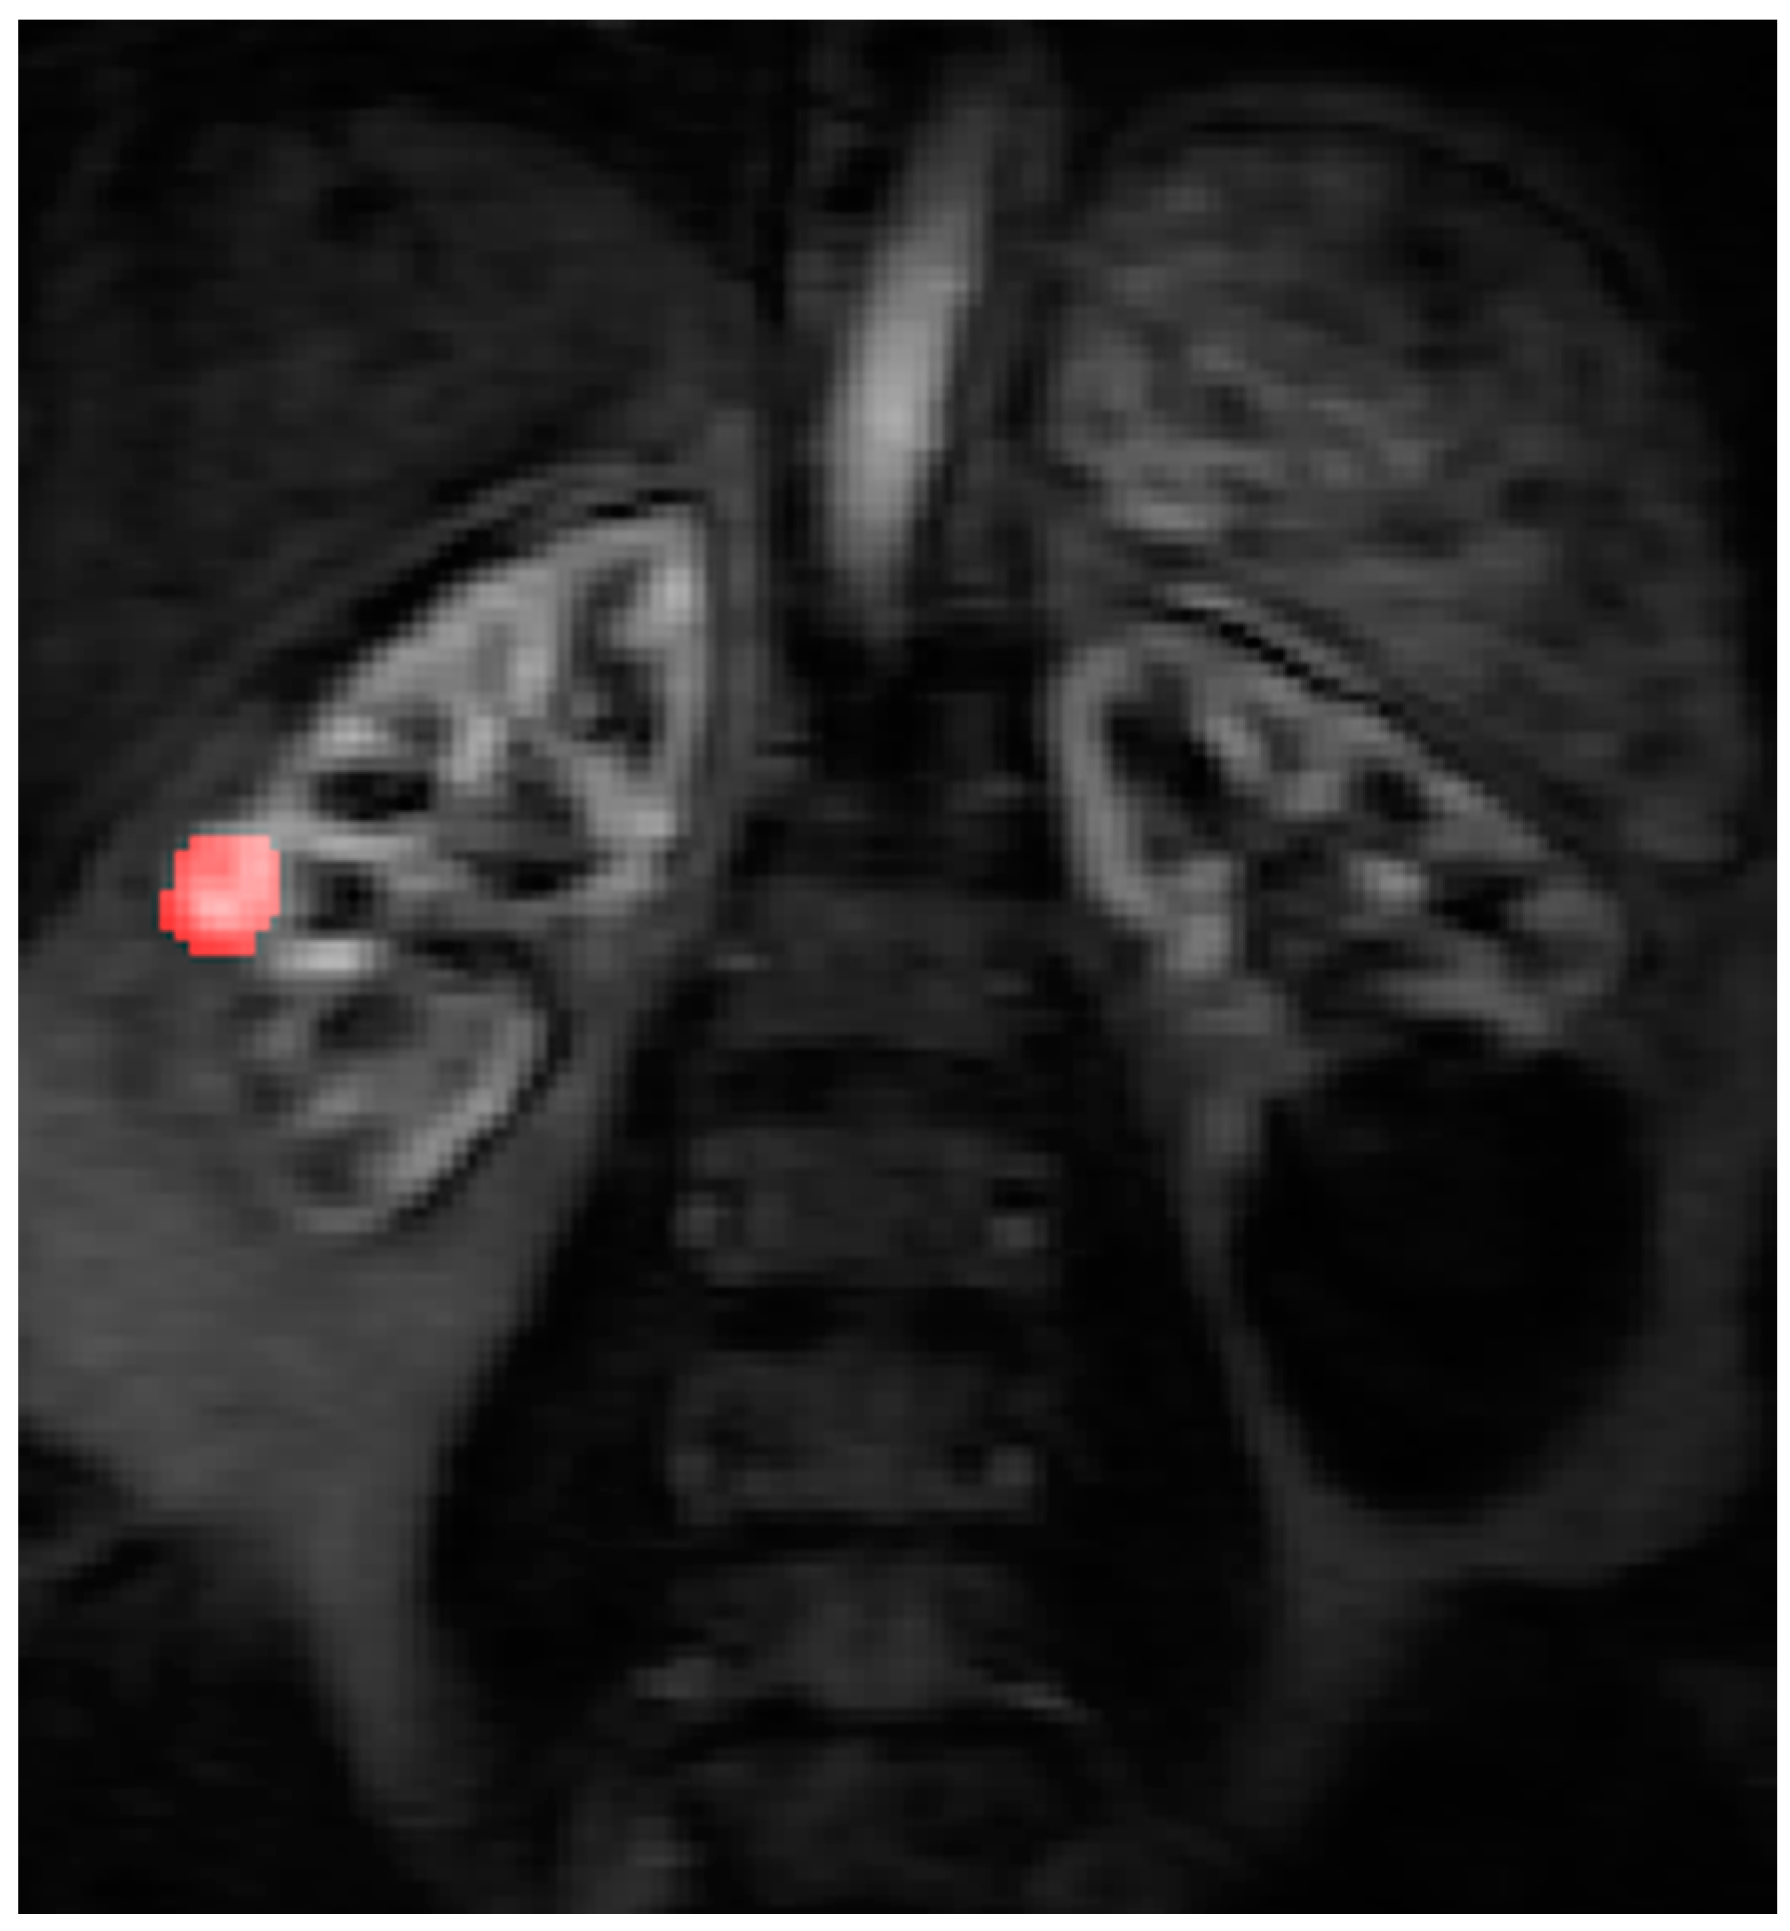

2.4. Data Post Processing

All the MR images were anonymized and post processing was performed offline by a single consultant radiologist with greater than 10 years of clinical experience (Dr Tze Min Wah). Images were uploaded into PMI 0.4 (Platform for Research in Medical Imaging Version 0.4 [13], which was running on a desktop PC. A standardized 4-voxel region was used to extract an arterial input function (AIF). This region of interest (ROI) was drawn inside the aorta at the approximate level of the origin of the vascular pedicles of the kidneys (Figure 1 and Figure 2).

Contrast agent concentration-time curves were approximated using relative change in signal (compared to baseline) against time [13]. To assist in identifying the tumour and drawing the ROI, a map of maximum contrast agent concentration was generated. Using the map, ROIs were drawn to encompass the renal tumour pre RFA (Figure 3) and the whole zone of ablation post RFA (Figure 4).

Figure 3. The right renal tumour is sited at the mid polar region of the kidney and there is a large renal cyst at the lower pole of the left kidney. The ROI is drawn on the maximum concentration map generated by Platform for Research in Medical Imaging (PMI) software before RFA treatment.